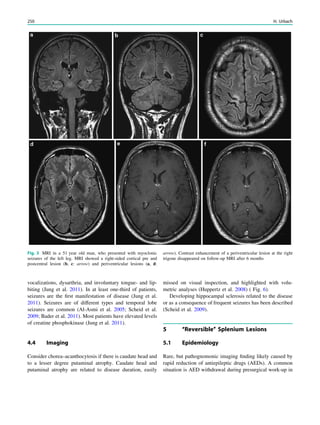

Fig. 1 An 8-year old girl presented with two focal motor seizures and

postictal left arm paralysis. MRI shows superior sagittal sinus

thrombosis (a–c, arrows) with two small hemorrhages at the gray

matter–white matter junction in the right frontal lobe (a, hollow

arrows)